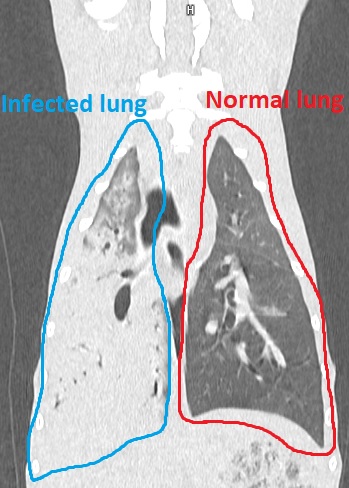

The pup had gone into renal failure and received treatment from our industry-leading emergency critical care team, with vets later discovering she also had a severe infection which caused pneumonia and most of her total lung tissue to turn into an abscess.

Part of the lung had to be removed, which Ella was recovering well from, but five days after surgery, she began to deteriorate due to a leak in the lung. She had to undergo another operation to seal the leak and remove some more of the damaged organ.